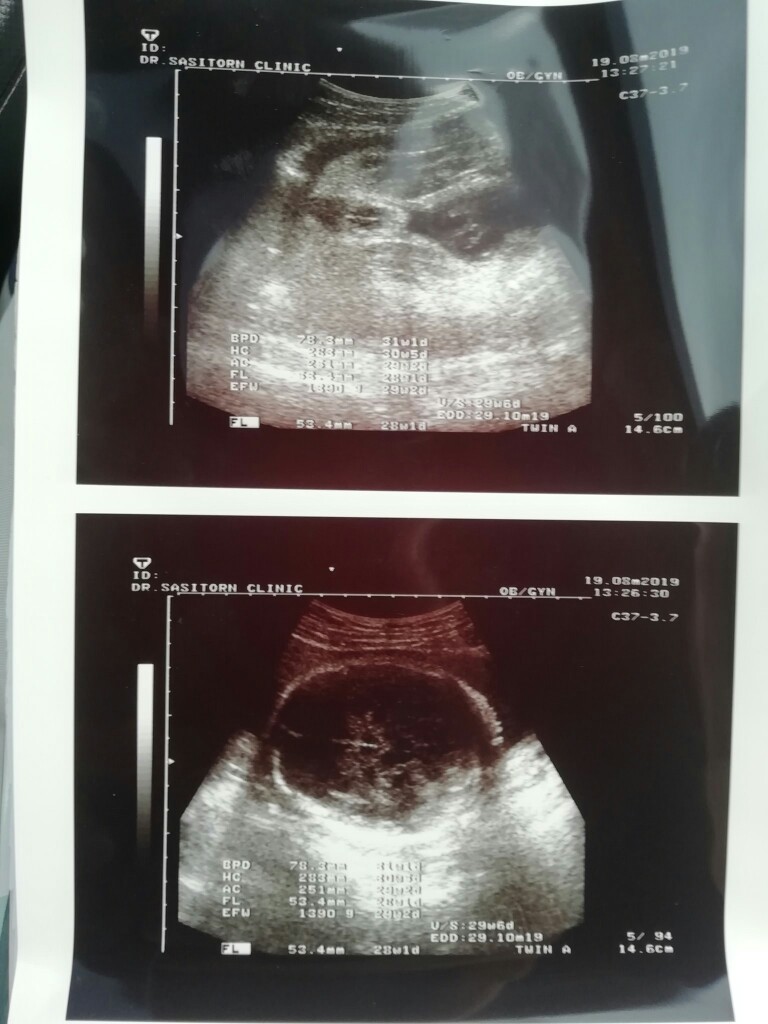

นี่7เดือนเลยจ้า ผู้หญิง